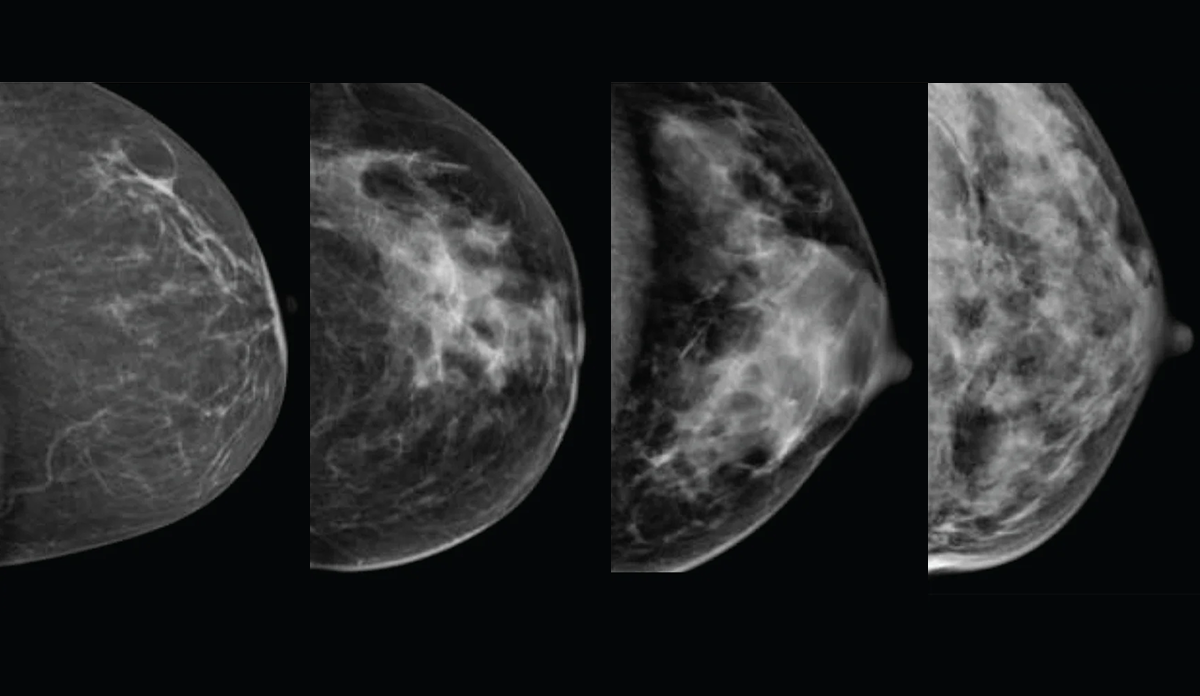

Breast density describes the ratio of fibrous and glandular tissue to fatty tissue in your breasts. On a mammogram, denser tissue appears white like many cancers which makes it harder to spot changes.

The American College of Radiology's Breast Imaging Reporting and Data System (BI-RADS) is used to describe breast density seen on the mammogram. The levels of density, which are included in a mammogram report are:

A.   Almost entirely fatty means that the breasts are almost entirely made up of fatty tissue. There is very little dense breast tissue.

B.   Scattered areas of fibroglandular density means the breasts are mostly made up of fatty tissue. But there are some scattered areas of dense breast tissue.

C.   Heterogeneously dense means that most of the breast tissue is dense breast tissue. But there are some areas of fatty tissue.

D.   Extremely dense means that nearly all of the breast tissue is dense breast tissue. There is very little fatty tissue.

If your results are in categories C or D we say that you have dense breast tissue.